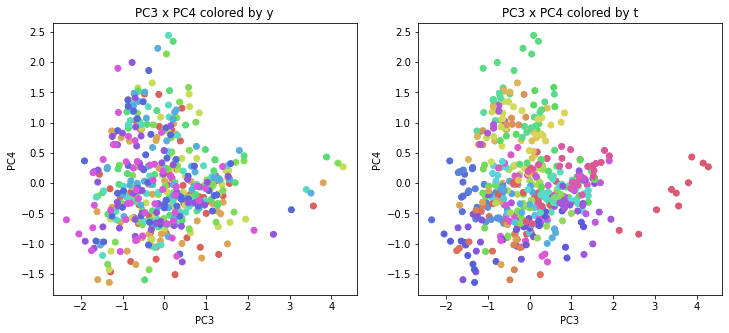

PCAの結果の第n主成分をPCnと表記します。

医療費データの場合と同様に、PCAの結果を見やすく表示するため、seabornのカラーパレットを使って、年月別、都道府県別に色分けして図示してみます(左側が年月別に色分け、右側が都道府県別に色分け)。PC1~PC8まで表示しました。

医療費データの場合ほどはっきりとはしていませんが、PC2が概ね時間の経過を表す成分で、残りの成分が時点によって変わらない地域の特徴を表す成分となっているようです。

また、PC1×PC3を見ると、47沖縄が他の都道府県からかなり離れたところに位置しており、沖縄の地域差が際立っているのが分かります。これは、以前別の記事で年齢階級のない健診データでPCAを実行した場合と似た結果となっています。

今回は、医療費データと同様に、健診データ240次元についてPCAを実行してみました。PCAの結果、医療費データの場合ほどはっきりしとはしていませんが、第2主成分が概ね時間の経過を表す成分で、時間軸に沿った全体的な動き(全国的な動き)を表しており、それ以外の成分が地域の特徴を表す成分で、この10年間あまり変わっていないことがわかりました。